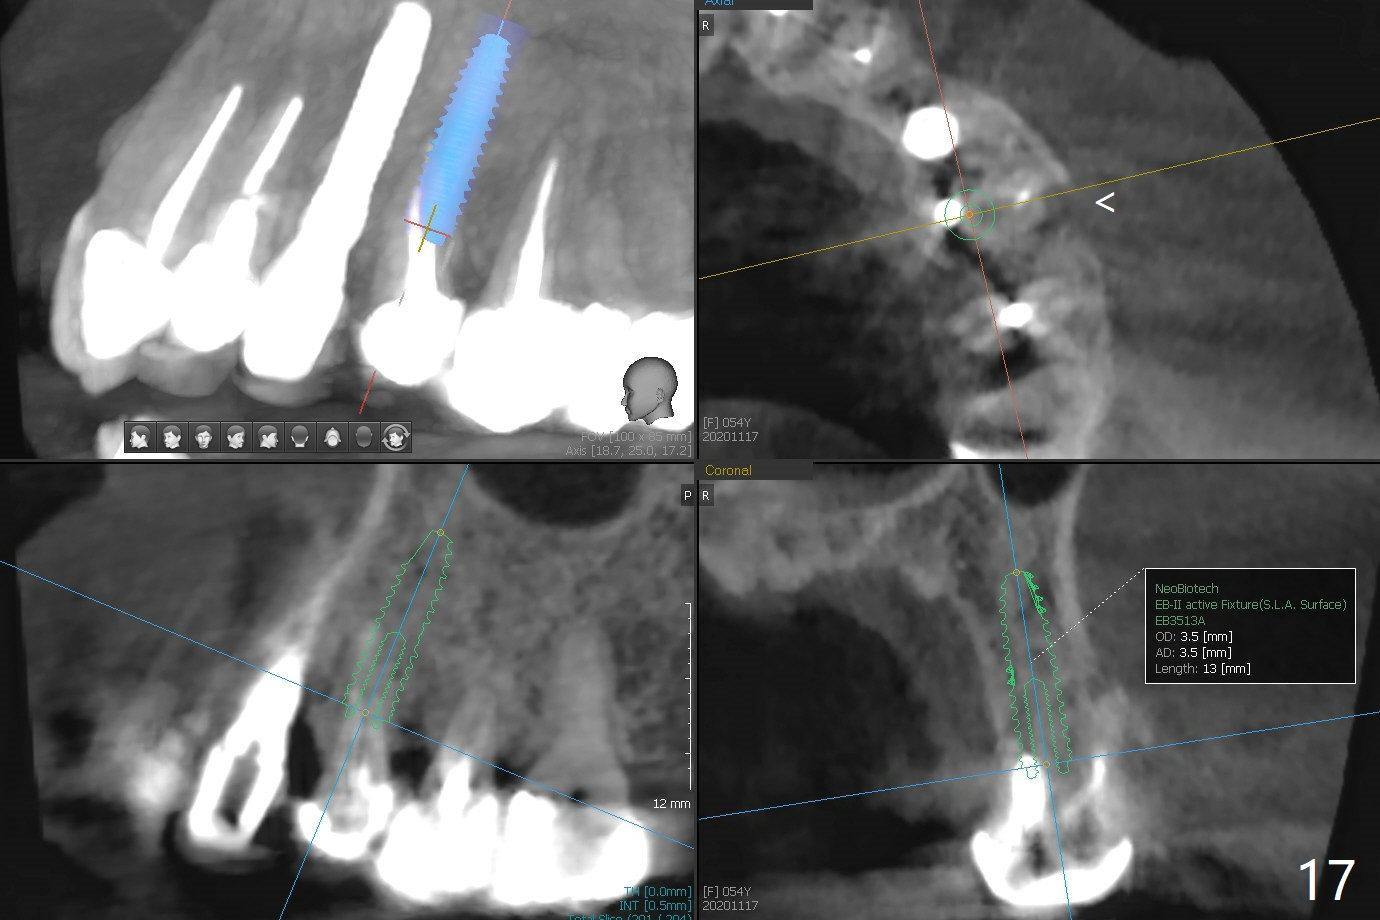

In spite of severe apical infection (Fig1,2 *), a thin narrow strip of the buccal plate (arrowheads, corresponding to the keratinized gingiva) is present when the tooth #11 is extracted. The thin bone keeps the bulging alveolus, i.e., reservoir for bone graft (Vanilla/Osteogen Fig.4 *) after placement of a 3.8x16 mm implant (Fig.3,4). A 4.5x1 mm temporary abutment, placed and trimmed for an immediate provisional, seems to be short in cuff. When an implant is placed deep to prevent periimplantitis, the cuff should be longer, i.e., 3 mm. X-ray should be taken for the depth confirmation after temporary abutment placement. Eight days postop, the mesial gingiva erythema has subsided (Fig.5 < (P: provisional)), while the apical swelling is no longer tender and most likely due to packed bone graft (*). Panoramic X-ray taken 2 weeks postop shows the clearance from the nasal cavity or the maxillary sinus (Fig.6). While the hard tissue around the implant seems to be healthy 5 months postop (Fig.7), the soft tissue is not (Fig.8). The temporary abutment is changed to a cemented one (4.5x5(2) mm) for impression (Fig.8). Since the neighboring crowns are PFM (Fig.6), the new crown will be made of the same material for shade match. Indeed PFM helps shade match in this case as well (Fig.9,10). Switching abutments (from temporary to cemented) makes it difficult to seat the crown. Post cementation X-ray leaves record for future contact loosening. The buccal gingiva remains erythematous associated with open margin (Fig.11 >) 1 year 4 months post cementation. There is no obvious bone loss 1 year 4 months post cementation (Fig.12). It appears that the crown and abutment need to be changed. Although the gingival margin remains erythematous, the gingival hemorrhage is basically lacking due to better oral hygiene during Shelter at Home (1 year 9 months post cementation, Fig.13). Change in abutment and crown will be conducted post coronavirus pandemic. In fact the abutment is incompletely seated (Fig.14 <). In addition, the tooth #12 is symptomatic with PARL associated with the buccal root (*). CBCT indicates possible buccal root fracture (Fig.15,16 ^) and loss of the buccal plate (Fig.16 <).